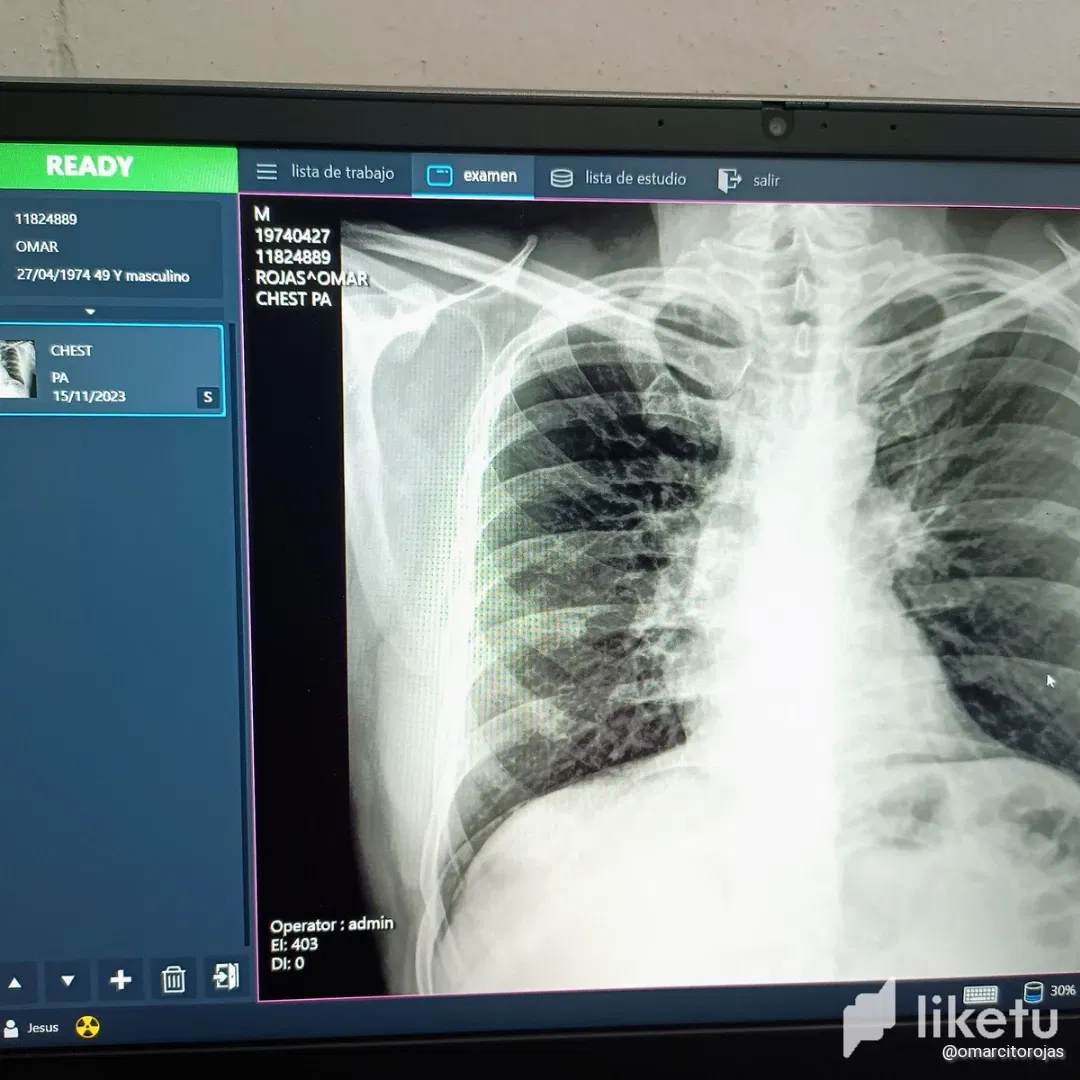

<liketuimages> <center>          </center> </liketuimages>  <div class="text-justify"><p>Truly the situation that I have had to live, is something, as we say in our land, unbearable. Medically fulfilling three treatments and again I have had to return to the clinic, to definitely examine me with a specialist, even knowing the expense incurred and that now a specialist generates higher costs, but everything is for my sake and to generate a diagnosis that leads to full recovery. I had already contacted the internist and she had sent me for some lab tests and a chest x-ray to check how my lungs were doing; well, apparently they were not very well. The lab results showed a type of infection and the chest x-ray corroborated it, since the lungs were congested and swollen, they asked me if I was a smoker and I had never touched a cigarette in my life. All this was the result of previous episodes that were not cured correctly and now this negative factor was noticeable. Another thing that the doctor saw was that the ribs did not have the regulatory arch, but were very straight, also a product of all the previous infectious processes. According to the doctor, the ribs, as I have them, prevent the air from coming out correctly. The truth is that this is the fourth treatment, which is long term; however, I was to be given a steroid injection immediately. After buying all the medicines, the injection was given to me in an outpatient clinic near home, while the remaining treatment of antibiotics, a combination of allergy medicine, cough syrup and nebulizations would be long term. Well, the antibiotic for 7 days and nebulizations for 15 days three daily. The antiallergics and immunizers if I have to take them for at least three months. Little by little we will make progress and I have faith that this treatment will put an end to this calamity. # <center>**...Thanks for visiting...**</center> Photographs taken by Militza Nuñez from my tecno camon 18p phone.</p></div>   <div class="text-justify"><p>De verdad que la situación que me ha tocado vivir, es algo, como decimos en nuestra tierra, inaguantable. Médicamente cumpliendo tres tratamientos y nuevamente he tenido que volver a la clínica, para de forma definitiva examinarme con un especialista, aún sabiendo el gasto realizado y que ahora un especialista genera costos mayores; pero todo sea por mi bien y por generar un diagnóstico que conlleve a la recuperación total. Ya había contactado a la internista y ella me había mandado a realizar unos exámenes de laboratorio y una placa de tórax para constatar como se encontraban los pulmones; bueno, al parecer no estaban muy bien. Los resultados de laboratorio arrojaron un tipo de infección y la placa de tórax lo corroboró, ya que se notaban los pulmones congestionados e inflamados, me preguntaron si yo era fumador y en mi vida había tocado un cigarro. Todo esto producto de episodios anteriores que no fueron curados de forma correcta y ahora se notaba ese factor negativo. Otro cosa que vio la doctora, fue que las costillas no tenían el arco reglamentario, sino que estaban muy rectas, producto también de todos los procesos infecciosos anteriores. Según la doctora, las costillas así como las tengo, evita que el aire salga de forma correcta. Lo cierto es que este es el cuarto tratamiento, el cual es a largo plazo; sin embargo debían colocarme una inyección de esteroides de forma inmediata. Luego de comprar todos los medicamentos, la inyección me fue suministrada en un ambulatorio cerca de casa, mientras que el tratamiento restante a base de antibióticos, una combinación de antialérgicos, jarabe para la tos y nebulizaciones, serían a largo plazo. Bueno, el antibiótico por 7 días y las nebulizaciones por 15 días tres diarias. Los antialérgicos e inmunizadores si debo tomarlos mínimo tres meses. Poco a poco iremos avanzando y tengo fé de que este tratamiento acabe con esta calamidad. # <center>**<div class="phishy">...Gracias Por Visitar...</div>**</center> Fotografías tomadas por Militza Ñúñez desde mi teléfono tecno camon 18p  **Use of the [Deepl](https://www.deepl.com/es/translator-mobile) translator to translate texts into English</p></div>** --- For the best experience view this post on [Liketu](https://liketu.com/@omarcitorojas/back-to-the-clinic-eng-esp)